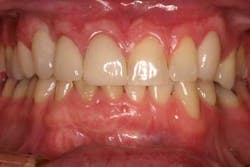

Immediately post-insertion, a periapical radiolucency was detected on the post-insertion radiograph on tooth No. 7 and the patient was immediately sent for root canal therapy. Four months was allowed for implant integration. At the time of Stage II, a noninvasive punch tissue technique was employed and a 3 mm healing abutment was placed. At the time of impression, an open tray technique was used and a custom abutment was selected. Because of the patient’s canine guidance occlusion, a porcelain-fused-to-metal crown was selected along with all-ceramic crowns on teeth Nos. 5 and 7.

One year post-insertion radiographs indicate that bone levels around the implant remain stable. Clinical results 1.5 years post-insertion reveal gingival levels to be stable and healthy, and the patient is very pleased with the esthetic result of his treatment.